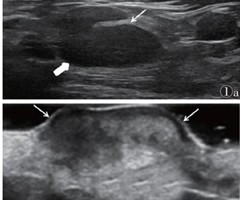

婴儿卡介苗腋窝反应性淋巴结炎超声声像图特征分析

[摘要]目的:探讨超声在婴儿卡介苗腋窝反应性淋巴结炎(BCG-itis)诊断中的应用价值。方法:回顾性分析28例经病理证实的腋窝BCG-itis患儿的超声声像图特征,观察病变淋巴结的长短径比值、形态、边界、淋巴结门、血流情况,并进行分区、分...